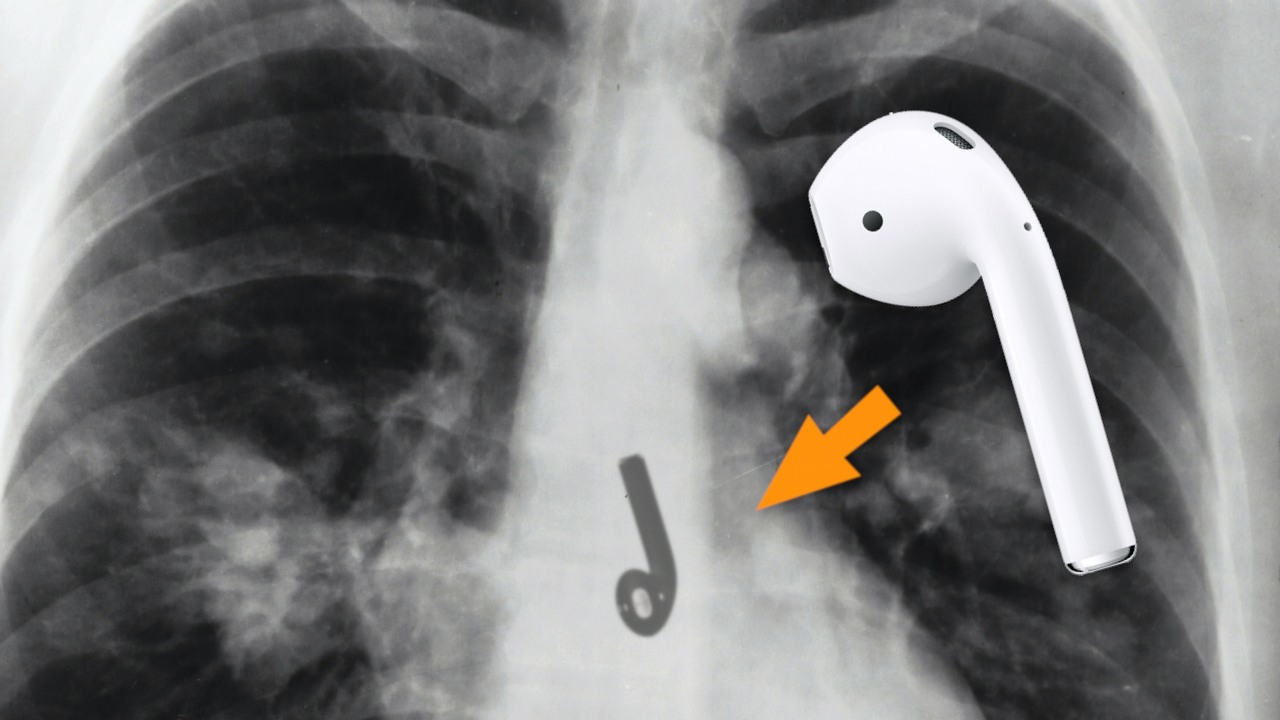

Pewien mężczyzna odczuwał dyskomfort podczas picia wody i ucisk w klatce piersiowej. Czyżby objawy koronawirusa? Otóż nie, prześwietlenie pokazało, że w jego przełyku tkwi słuchawka AirPods, połknięta podczas snu.

Bradford Gauthier mieszka w Worcester, mieście w stanie Massachusetts (USA). Pewnego dnia obudził się i chciał napić wody. Jednak miał z tym pewien problem – nie mógł jej przełknąć. Dodatkowo odczuwał ucisk w klatce piersiowej. Nie przejął się jednak zbytnio tymi objawami i poszedł poszukać swoich słuchawek bezprzewodowych, gdyż przypomniał sobie, że słuchał muzyki przed snem. Przeszukanie sypialni ujawniło jednak tylko jedną sztukę. Jego żona zasugerowała możliwość połknięcia i Brad pojechał na pogotowie. Musiał być zdumiony, gdy zdjęcie rentgenowskie potwierdziło, że faktycznie jedna słuchawka AirPods tkwi w dolnej części przełyku.

Mężczyzna dzień wcześniej sporo odśnieżał i poszedł spać zmęczony. Przed snem postanowił posłuchać muzyki i jak widać, była to błędna decyzja. Wysiłek sprawił, że szybko zasnął, nie odkładając słuchawek. Jedna z nich musiała się dostać do ust, a potem do przełyku. Po szybkiej diagnozie Bradowi wykonano endoskopię i urządzenie z organizmu zostało wyjęte. Objawy ustąpiły i co najciekawsze, okazało się, że słuchawka AirPods nadal działa (źródło):